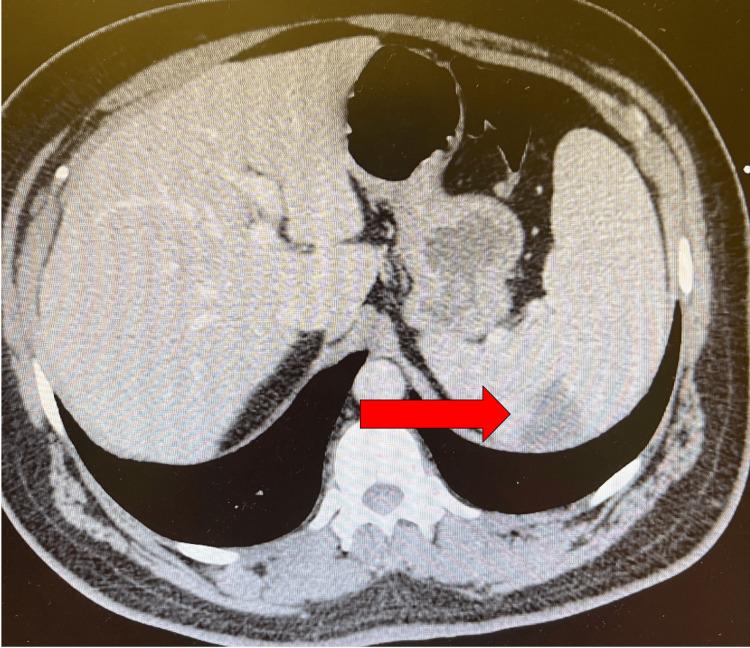

A Case Report of Subacute Infective Endocarditis Presenting With Extreme Weight Loss, Aortic Regurgitation, and Splenic Infarct.

We present an insightful case of a middle-aged male who presented to the emergency department (ED) with complaints of excessive weight loss, accompanied by shortness of breath and vomiting. Consequently, this case explores many facets of the pathophysiology of infective endocarditis (IE), including but not limited to the most heavily implicated microorganisms, symptoms, predispositions, and disease outcomes. IE is a pathology of variable presentation with uniquely extensive diagnostic criteria, making it a fascinating topic of medical discussion.